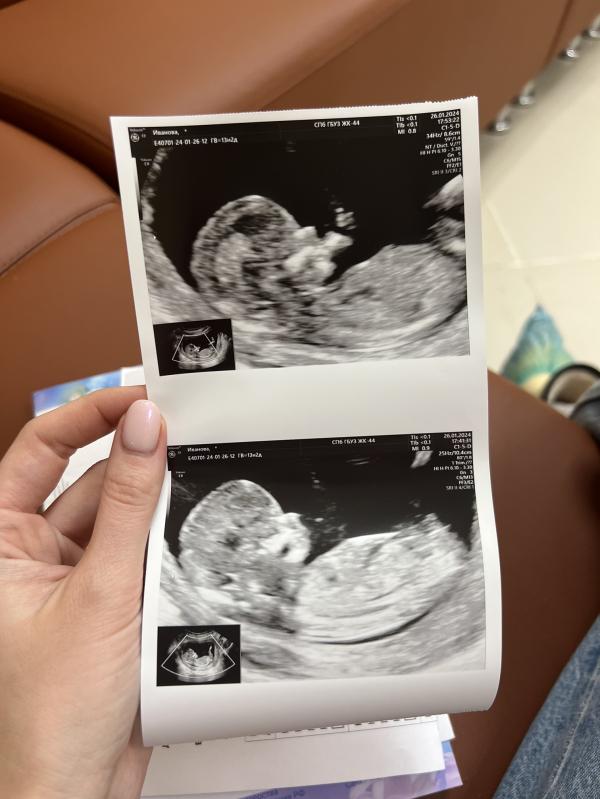

Вчера у нас был первый скрининг и мы наконец то познакомились с малышом ❤️

Все время он пускал пузыри ртом😂 активничал и вовсю махал руками, видимо очень хотел сказать мне: «Мама, я тут! Привет»😃